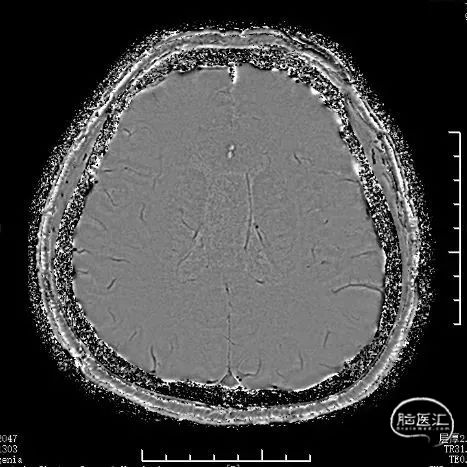

治疗之前3D和工作位(测量病变处近远端血管管径,M1近端1.9mm,M1远端1.7mm)。

全麻下,通过同轴技术泥鳅导丝、5F VTK将6F长鞘置于右侧颈总动脉,撤出微导丝及VTK,随后路图下泥鳅导丝携6F Tethys®中间导引导管置于右侧颈内动脉C4段。撤出泥鳅导丝,在6F Tethys®中间导引导管路图下,顺导丝(交换导丝)将加奇SacSpeed® 1.75×12mm球囊置于狭窄段,路图下精确定位,以1atm/30s速度缓慢扩张球囊至6atm左右,释放球囊压力。造影提示右侧大脑中动脉狭窄明显改善,瘤样突起减少,撤出球囊。